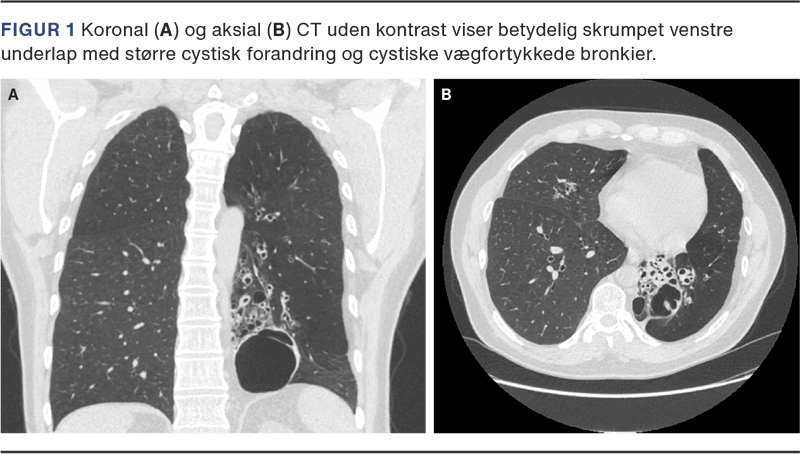

Der opstod nyt anfald af epistaxis ti timer efter operationen, denne gang ledsaget af sikker hæmoptyse. Røntgen af thorax viste bronkieektasier og bullaedannelse i venstre underlap. Ved gennemgang af tidligere billeddiagnostik forelå CT af thorax, som var udført i andet udredningsforløb (Figur 1). På skanningen var venstre underlap cystisk omdannet, hvilket på scanningstidspunktet var tolket som postinfektiøse forandringer og grundet fravær af kliniske luftvejssymptomer var der ikke udredt yderligere.

Patienten blev overflyttet til thoraxkirurgisk afdeling, hvor bronkoskopi afslørede flere koagler i luftvejene. Efter oprensning blev en mulig blødningskilde fundet i venstre underlap. Ved torakotomi fandt man en cystisk omdannet venstre underlap, som blev excideret. Materialet blev ved patologisk undersøgelse fundet foreneligt med en congenital pulmonary airway malformation (CPAM) og klassificeret som Stocker type I.